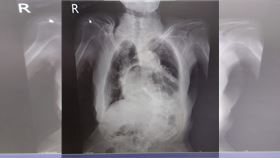

長期咳嗽別輕忽!小心「咳到胃翻出來」!

千萬不要輕忽長期咳嗽的症狀,否則恐後患無窮!台北市立...